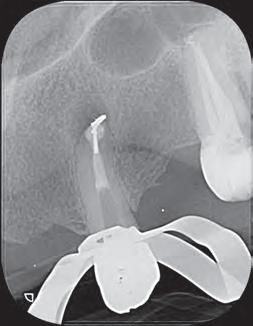

El retratamiento endodóntico comenzó con el acceso a la cámara pulpar usando una Broca Dental Predator Turbo (Angelus - Londrina - Brasil). El cemento en torno al vástago del cono de plata fue removido con una punta ultrasónica E7D (Helse Ultrasonic-Brasil) (Figura 2). Después de la exposición de la parte coronaria del cono de plata, una E5 - Punta Cónica Larga Ultrasónica (Helse Ultrasonics - Brasil) fue usada para vibrar el cuerpo del cono de plata. Aunque la baja potencia ultrasónica ajustada en un 15%, ocurrió una separación (Figura 3). Debido a la falta de adaptación del material de la obturación en el tercio apical, parte del fragmento de cono de plata fue removida de la lesión periapical.

Figura 2 - Vista del conducto obturado de la parte coronaria del cono de plata

Figura 3 - Primera separación del cono de plata

El modelo del conducto radicular se realizó utilizando Lima Reciproc R25 (VDW - Alemania) seguido por Lima Reciproc Azul RB50 (VDWAlemania). Durante el retratamiento endodóntico, se realizó una irrigación abundante con un 2,5% de hipoclorito de sodio. Después de varios intentos para quitar la parte remanente del cono de plata, otra separación ocurrió (Figura 4). La parte del cono de plata fue removida del canal. Sin embargo, el otro fragmento no pudo ser eliminado.

Figura 4 - Expulsión del cono de plata

En esta fase del tratamiento, el control de desinfección adecuado no se había alcanzado. La presencia del fragmento, no permitía una desinfección apropiada del conducto radicular. Debido a esto, el dolor espontáneo, aunque disminuido, no cesó. Como resultado del fallo en el control adecuado de infección, una cirugía complementaria fue propuesta para remover el fragmento apical. Antes de entrar en la microcirugía, el conducto radicular estaba concluido.

El retratamiento endodóntico del conducto obturado fue realizado con un enjuague final con EDTA 17% pasivamente activado ultrasonicamente, seguido por obturación del conducto radicular usando conos de gutapercha con BIO-C® REPAIR (Angelus - Brasil). BIO-C® REPAIR es un nuevo Cemento Endodóntico Biocerámico Listo para Uso. Puede ser colocado de la jeringa directamente al conducto radicular. Los conos de gutapercha fueron compactados con una técnica de compactación fría vertical (Figura 5).

Figura 5 - Obturación endodóntica